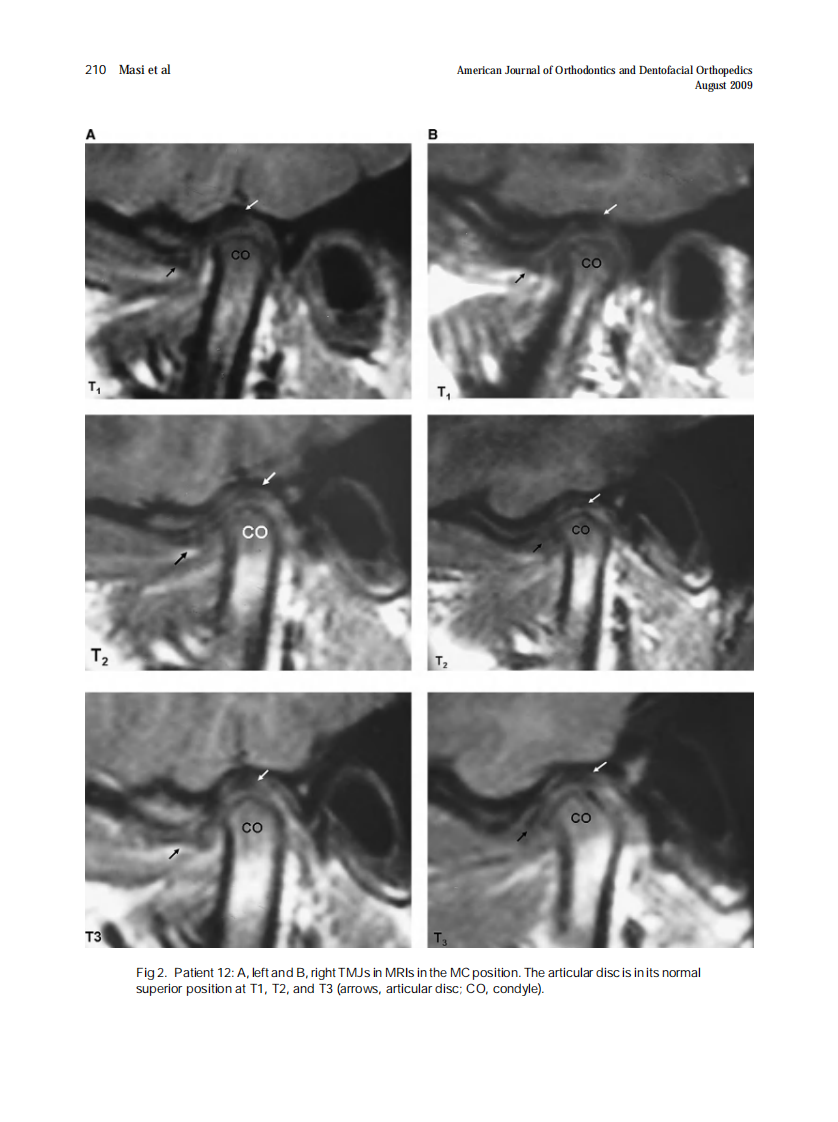

AJO-DO

2009_136_2_207_217.pdf